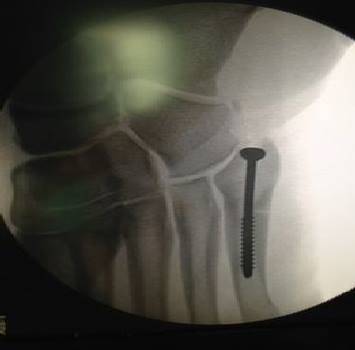

XABI ALONSO CHIODO FOTO – A prima vista può sembrare qualcosa di incredibile invece l’immagine in foto non è altro che la radiografia del piede di Xabi Alonso sottoposto alle cure dei medici in modo…particolare. Il centrocampista del Real Madrid si è infatti fratturato il quinto metatarso del piede destro ed è stato operato a Murcia per cercare il recupero nel minor tempo possibile. Per rendere Xabi più preciso al momento del rientro è stato inserito un chiodo all’interno del piede infortunato per sistemare la rottura.